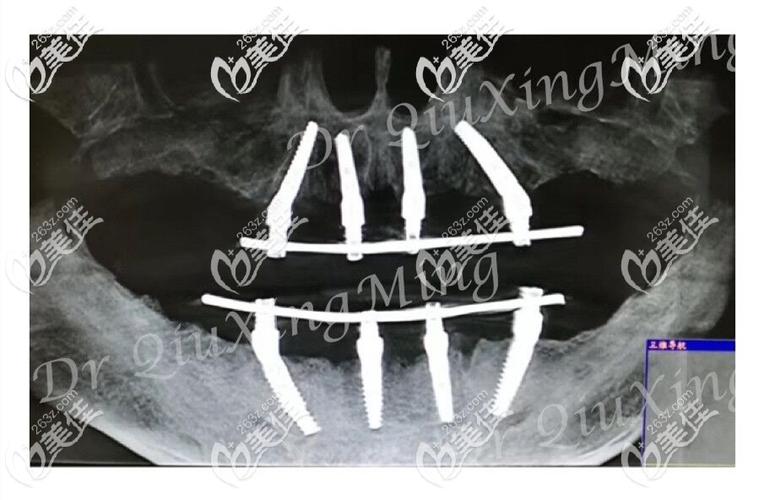

术前评估与设计:通过CBCT(锥形束CT)获取牙槽骨三维数据,在植牙图中标注关键解剖结构(如上颌窦底、下牙槽神经管),模拟种植体植入位置、角度及深度,确保避开危险区域,同时结合口腔模型,设计牙冠的形态、排列及咬合关系。

种植体植入:术中在牙槽骨上制备种植窝洞,按照植牙图设计的角度植入4颗种植体(常用直径4.0-5.0mm、长度10-13mm的钛种植体),前牙区垂直植入,后牙区倾斜植入,确保种植体尖端位于致密骨层以获得初期稳定性。